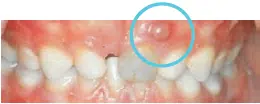

![Mund hvor fortand er blevet blå](https://gladsaxe.dk/i/MOLIRIMEDIA/b271f950-d433-472f-d508-08dc36def874?width=800)    ![Mund der viser en tandbyld over fortanden](https://gladsaxe.dk/i/MOLIRIMEDIA/d1da5415-c3f8-4ca2-d55b-08dc36def874?width=800)

På det første billede er en tand som har været slået og er blevet mørk. På det andet billede er der kommet en tandbyld ved en tand, som er slået. Dette er tegn på infektion. Det er vigtigt, at I henvender jer til tandklinikken.